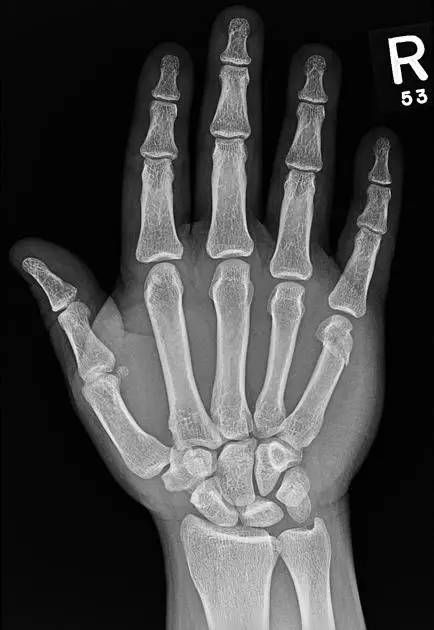

7. Boxer's 骨折

第 5 掌骨颈骨折伴有掌骨头向掌侧移位。

(来源:Radiopaedia)